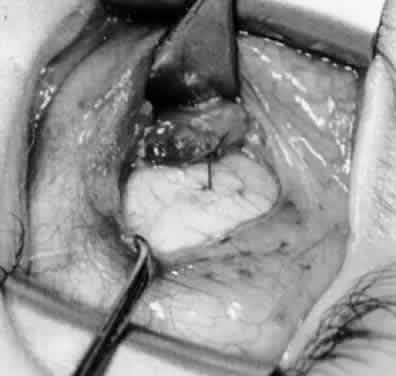

Fig. 21. A hemostat is placed adjacent to the insertion of the right inferior oblique muscle.

Fig. 22. An Aebli scissor is used to section the inferior oblique muscle from the globe.

Fig. 23. The inferior oblique muscle is drawn into the operative field with a hemostat. This step may be used for the recession procedure if the surgeon is concerned about the placement of the 6-0 Vicryl suture while the muscle is attached to the globe in the proximity of the macula. The recession sequence would follow after the placement of the suture while the muscle is grasped in the hemostat.